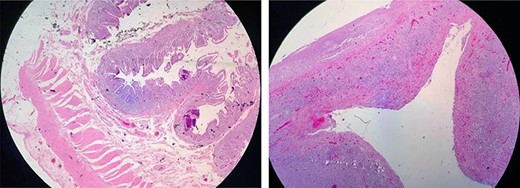

A 64-year-old woman presented with a history of untreated thyroid cancer and chronic diarrhea for 7 months without a diagnosis. The patient presented to the emergency department with sudden abdominal pain of moderate intensity and of a colicky quality, localized to the mesogastrium and irradiating to the hypogastrium, accompanied by several episodes of vomiting. Physical examination showed a distended abdomen that was painful on palpation at the hypogastrium and vague peritoneal symptoms. Additional tests showed neutrophilic leukocytosis and moderate hypokalemia. A computed tomography scan of the abdomen and pelvis with and without contrast revealed multiple mesenteric lymph nodes in addition to ileal intestinal enhancement with a small amount of free liquid in the abdominal cavity, a hydropic gallbladder and a distended appendix. A diagnostic laparoscopy was performed and later converted into an exploratory laparotomy because of the presence of free intestinal liquid in the cavity caused by small bowel perforation (Fig. 1A).

(A) Fibrinopurulent exudate and terminal ileal perforation at 20 cm from the ileocecal valve, measuring 0.3 cm in diameter. Pre-perforated areas are located at 40 and 60 cm from the ileocecal valve. (B) Resection of the ileum.

Ileal resection (Fig. 1B) with ostomy and abdominal lavage were performed, and a negative pressure drainage system was placed. The surgical procedure was performed without complications, and the patient was transported to the recovery room to begin antibiotic therapy.